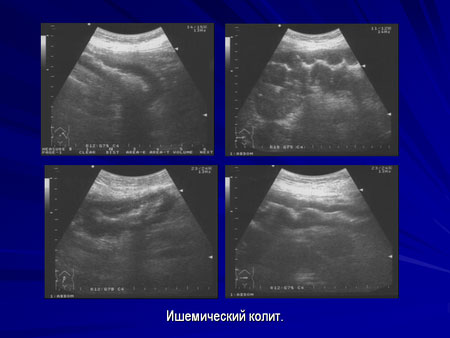

Ультразвуковая диагностика опухолевых заболеваний

ободочной и прямой кишок.

Часть 2: Дифференциальная диагностика.